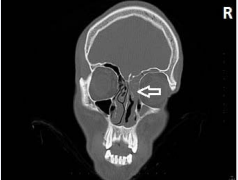

27 year-old male patient applied to emergency service in our hospital with on going and even increasing complaints of ptosis on eyelid, nasal and post-nasal drainage, pain around right eye and frontal side for 3 days. The patient was directed to us just after infection symptoms are determined on the same side during cranial CTtaken in emergency service for patient’s ptosis etiology. During ear-nose-throat examination of the patient, ptosis on right upper eyelid, purulent secretion in both nasal cavities, postnasal heavy purulent secretion were determined. The patient was conscious and general medication condition was fine. Fever was within range. WBC, sedimentation and CRPvalues were high in laboratory evaluation. It was evaluated that eye movements were free in every direction for both eyes, visual acuity was complete in both directions and light reflexes are exact. High density rise was determined inside of right maxillary, ethmoid, sphenoid and frontal sinus on right nasal cavity during paranasal sinus CT (Figure 1).

EParanasal sinus CT, coronal is showing inflammatory changes and high density in right maxillary, ethmoid and frontal sinuses.

Figure 1: EParanasal sinus CT, coronal is showing inflammatory changes and high density in right maxillary, ethmoid and frontal sinuses.